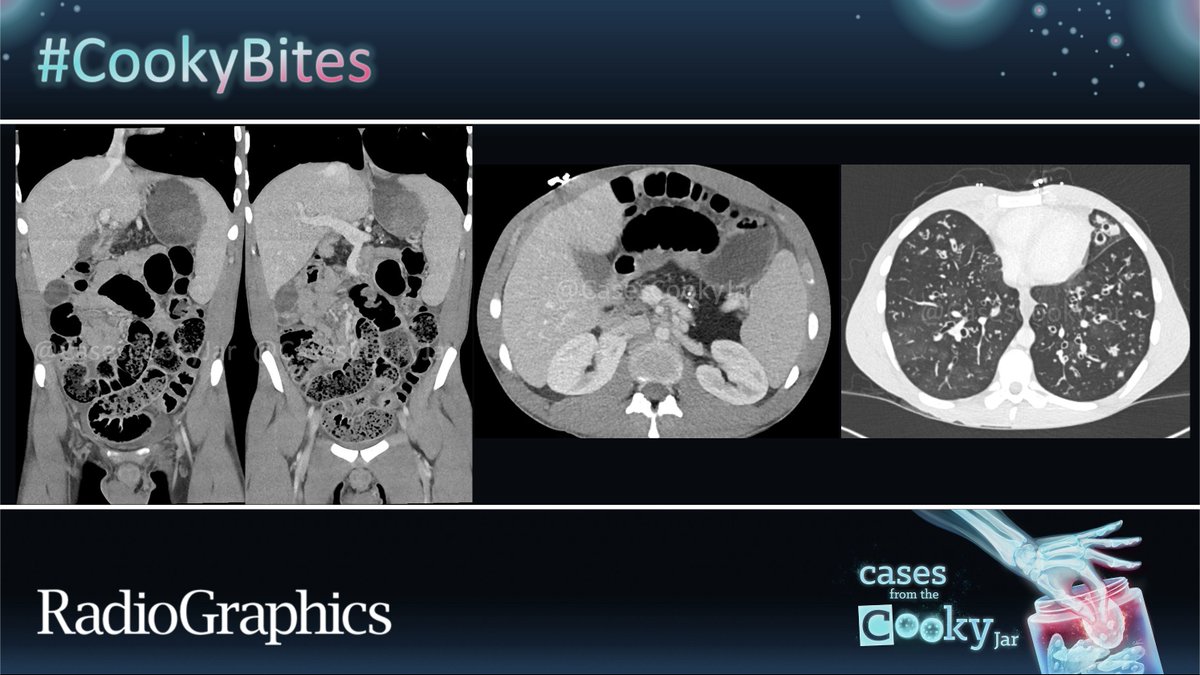

@CasesCookyJar

Cases From the Cooky Jar

4 days

55 M presents with fever and abdominal pain post-cholecystectomy. What is the diagnosis? 🧐🔍 We’ll post the answer in 24h. Share companion cases with us using #CookyBites #241. We will RT the best cases! #RGphx @cookyscan1 @RadioGraphics